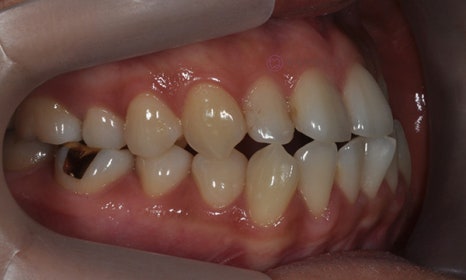

다음 케이스 역시 위 아래 중심선의 차이가 있어서 비대칭이 있어 보이는 케이스입니다. 중심선의 차이 뿐 아니라 앞니 및 어금니 부위에 거꾸로 물리는 반대교합이 관찰되고 있었습니다(원래는 위 치아가 아래 치아를 덮는 것이 정상적인 교합이나, 반대교합이란 위 치아가 아래 치아보다 더 안쪽으로 들어가서 물리는 교합을 말합니다).

2020.2

얼굴의 중심선과 위 치아의 중심선은 일치하여, 오른쪽 아래 작은 어금니를 발치하여 그 공간으로 아래 치열을 이동시켜줌으로써 중심선 및 교합을 개선하였습니다.

2021.2